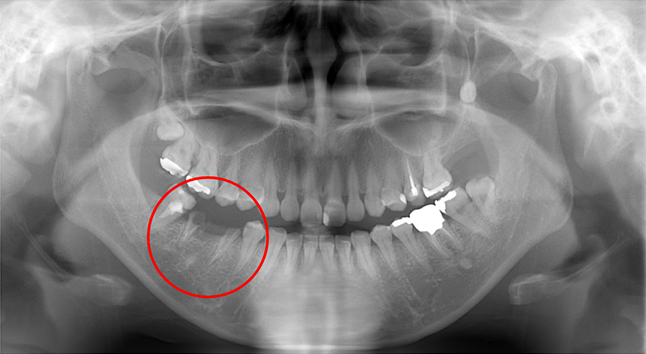

この患者さんは20台女性のまだ若い方ですが、下の奥歯が虫歯だったのを長く放置されていて悪くなり、残念ながら抜歯するしかなくなりました。

その後、骨にインプラントを埋めて、6週間後に歯型を取りセラミックの歯を作成、更にインプラント部位(赤丸部分)の前後の歯もセラミックで作成し装着しています。